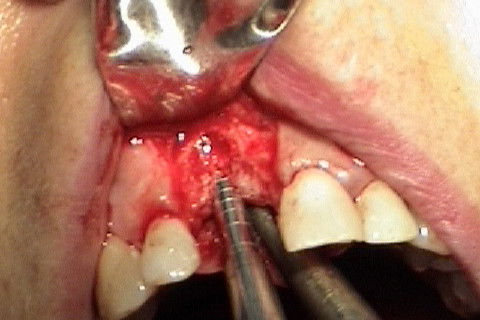

Perfuração terminada, pronta para inserção do implante